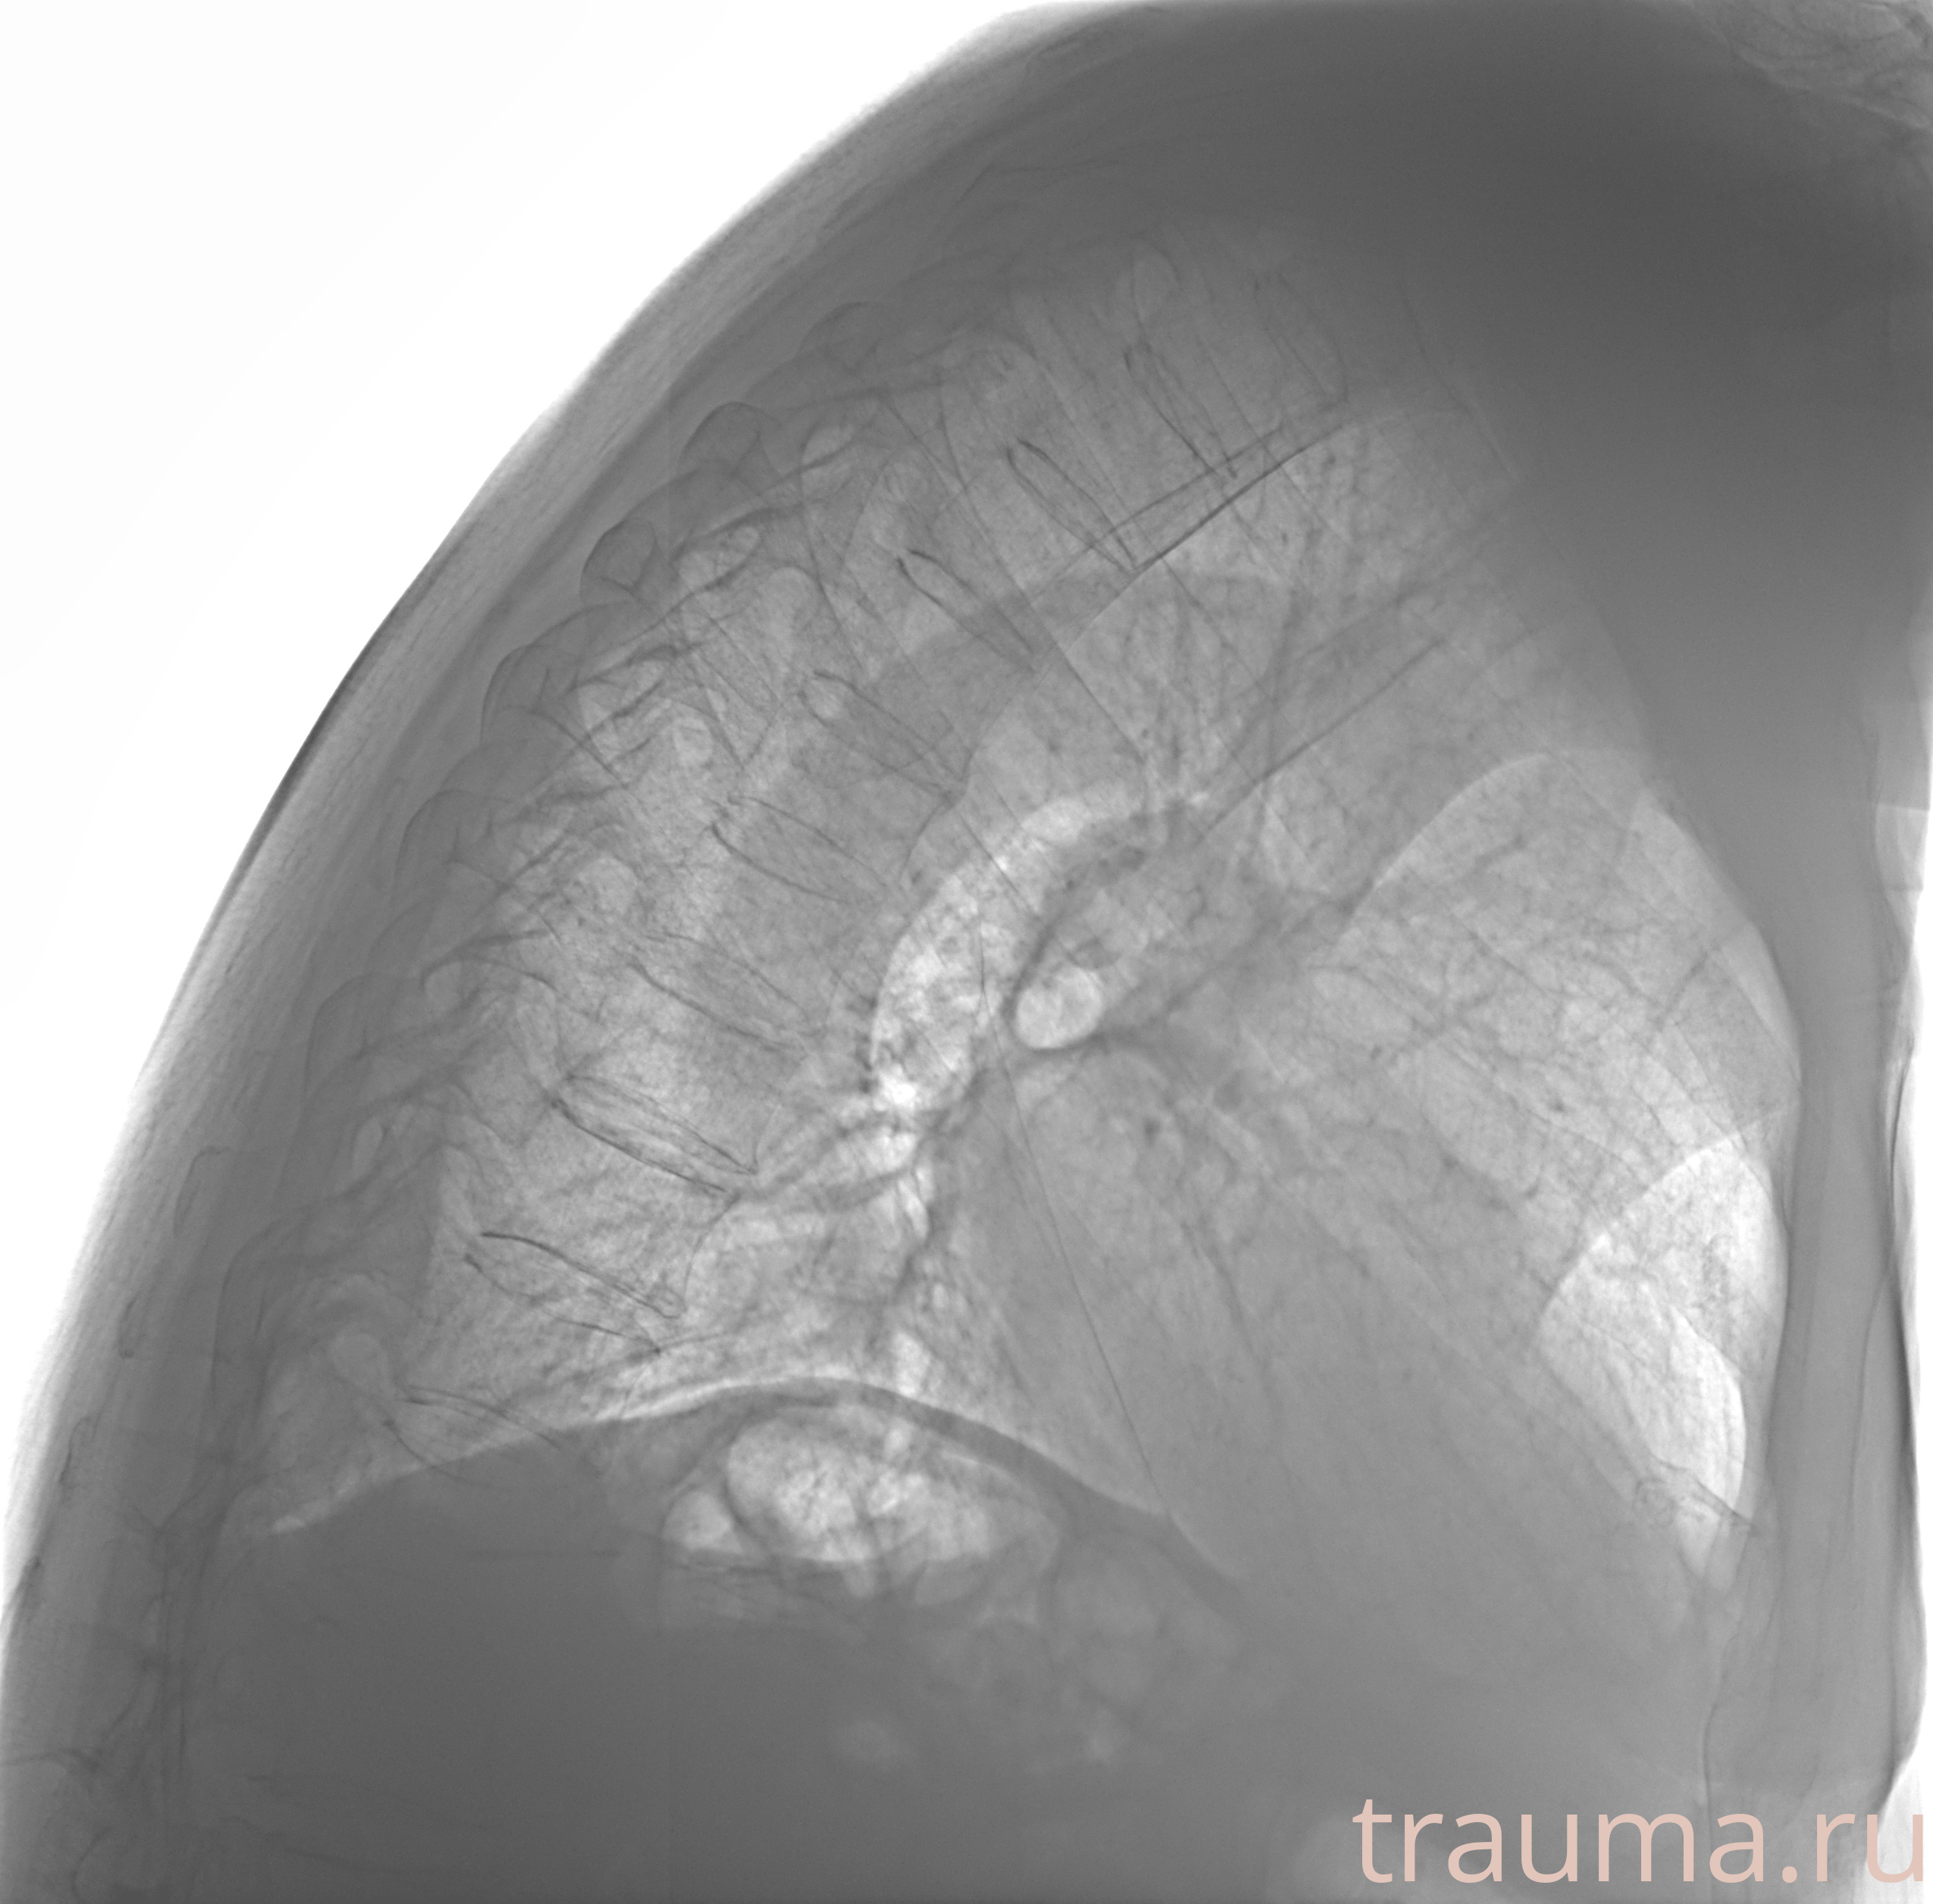

Рентгенограммы

Рентген на дому: по вашему адресу приезжает врач-рентгенолог, травматолог-ортопед с мобильным рентгеновским аппаратом, проводит диагностику травмы или заболевания, делает необходимые рентгенограммы, дает рекомендации по дальнейшему лечению. Получить качественные снимки в домашних условиях возможно благодаря уникальной методике, разработанной МосРентген Центром для института  Склифосовского